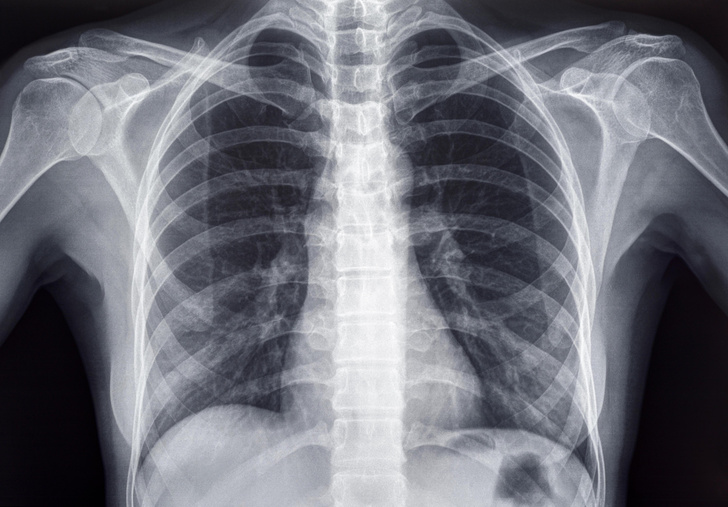

Найчастіше відхилення від стандартного набору виявляються лише під час обстеження — наприклад, на рентгені чи КТ.